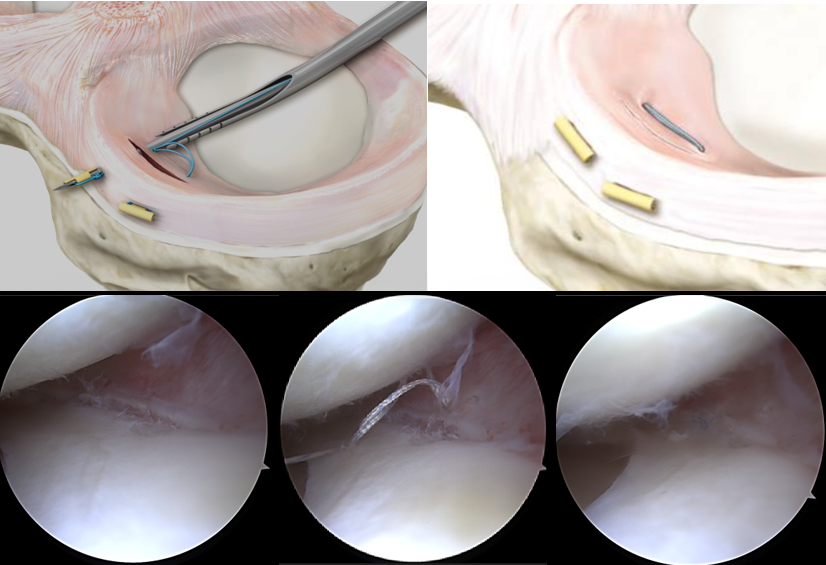

Wird eingesetzt, um begleitende Veränderungen wie Arthrose oder knöcherne Verletzungen auszuschließen – auch wenn der Meniskus selbst nicht sichtbar ist. - Arthroskopie (Gelenkspiegelung):

In seltenen Fällen notwendig, wenn MRT und klinische Befunde nicht eindeutig sind. Mit einer Mini-Kamera wird das Kniegelenk von innen beurteilt – oft mit der Option zur direkten Therapie.

Die Meniskusnaht ist ein arthroskopisches, gelenkerhaltendes Verfahren, bei dem der eingerissene Meniskusanteil mit feinen Nahttechniken fixiert wird. Ziel ist es, den Meniskus in seiner ursprünglichen Form zu rekonstruieren, damit er seine wichtige Funktion als Stoßdämpfer und Gelenkstabilisator weiterhin erfüllen kann.

2. Operative Therapie (arthroskopisch)

Bei größeren Rissen, anhaltenden Beschwerden oder mechanischer Blockade ist häufig ein minimalinvasiver Eingriff notwendig – meist im Rahmen einer Arthroskopie (Gelenkspiegelung).

Dabei kommen zwei Verfahren infrage:

A) Meniskusteilresektion

Bei der Meniskusteilresektion wird der beschädigte Teil des Meniskus mit feinen arthroskopischen Instrumenten entfernt. Anschließend wird der verbleibende Meniskus geglättet, um weitere Risse zu vermeiden.